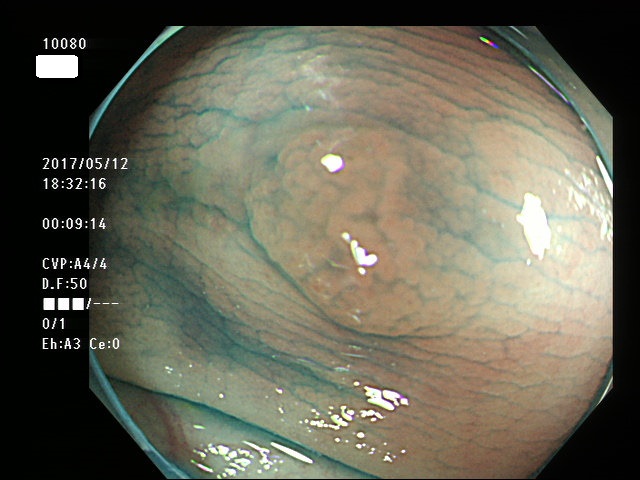

タイプ1・・・

右側に大型の過形成(SSAP)が数個、多発する。SSAPが直接、癌化すると考えられている